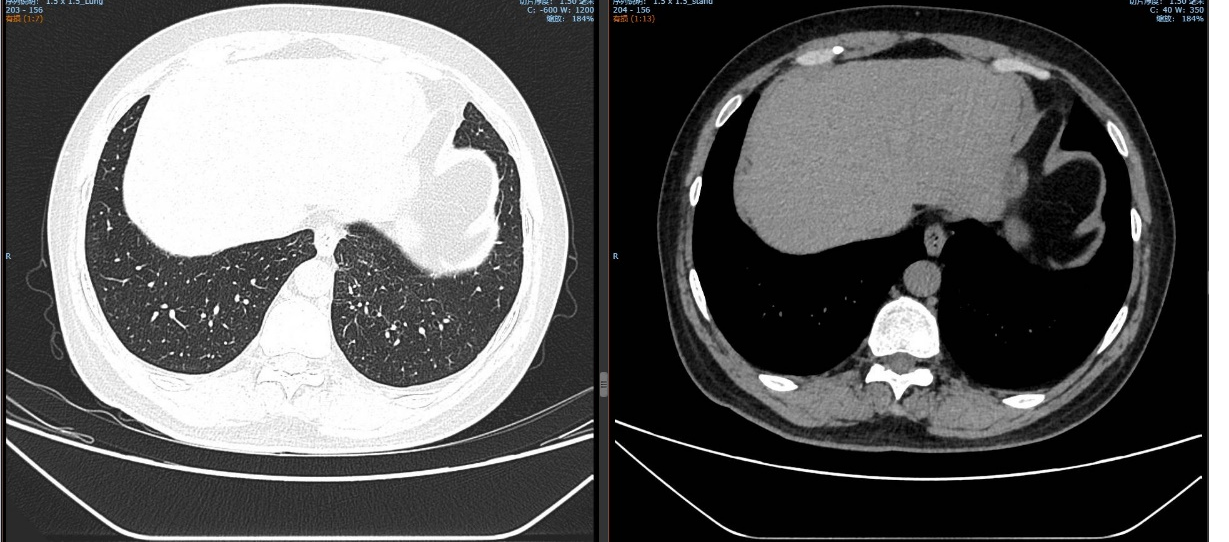

治疗5个月后(2025-05-07):复查CT显示左肺病灶显著缩小,达到PR,肺内结节明显吸收。

截至目前,PFS已超过10个月,病情持续稳定。